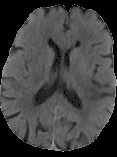

Accurate infarct segmentation in non-contrast CT (NCCT) images is a crucial step toward computer-aided acute ischemic stroke (AIS) assessment. In clinical practice, bilateral symmetric comparison of brain hemispheres is usually used to locate pathological abnormalities. Recent research has explored asymmetries to assist with AIS segmentation. However, most previous symmetry-based work mixed different types of asymmetries when evaluating their contribution to AIS. In this paper, we propose a novel Asymmetry Disentanglement Network (ADN) to automatically separate pathological asymmetries and intrinsic anatomical asymmetries in NCCTs for more effective and interpretable AIS segmentation. ADN first performs asymmetry disentanglement based on input NCCTs, which produces different types of 3D asymmetry maps. Then a synthetic, intrinsic-asymmetry-compensated and pathology-asymmetry-salient NCCT volume is generated and later used as input to a segmentation network. The training of ADN incorporates domain knowledge and adopts a tissue-type aware regularization loss function to encourage clinically-meaningful pathological asymmetry extraction. Coupled with an unsupervised 3D transformation network, ADN achieves state-of-the-art AIS segmentation performance on a public NCCT dataset. In addition to the superior performance, we believe the learned clinically-interpretable asymmetry maps can also provide insights towards a better understanding of AIS assessment. Our code is available at https://github.com/nihaomiao/MICCAI22_ADN.